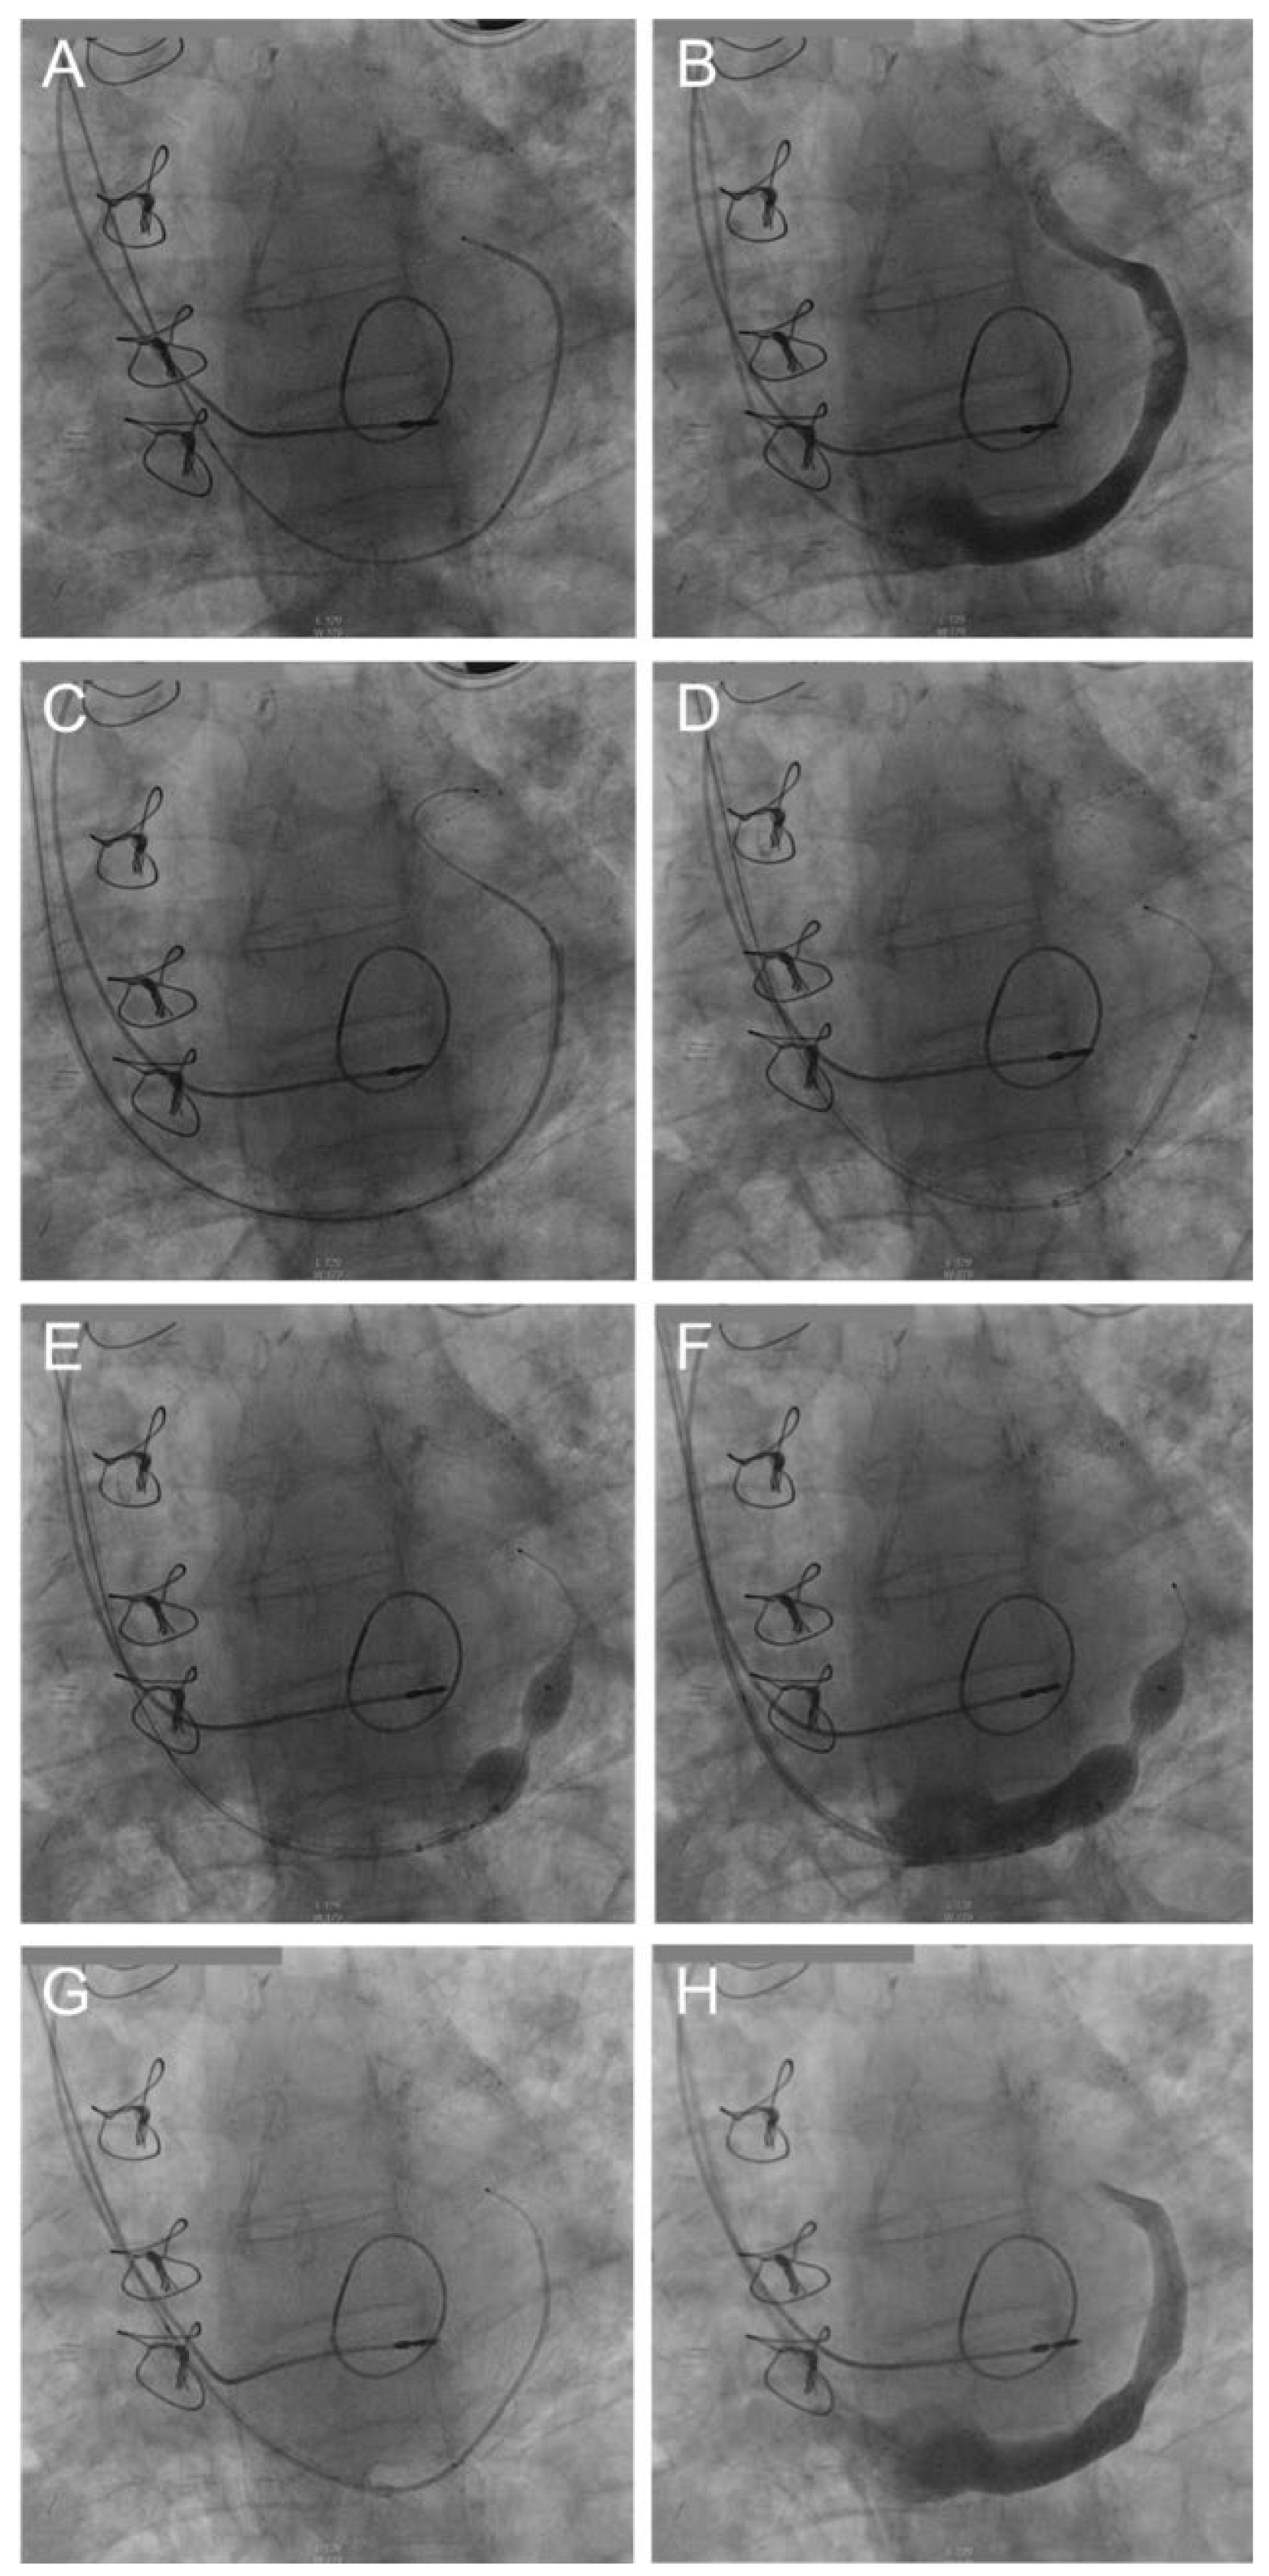

Stepwise description of the implantation of the device